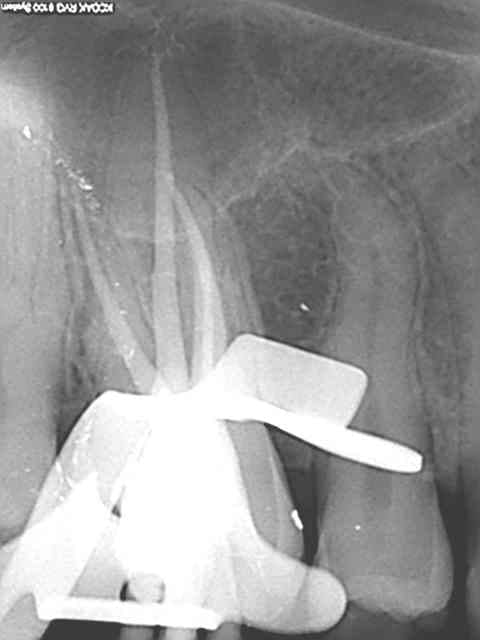

Tu crois que si je travaille sous dique et que je jette un r25 et un saf par pulpec et que je me fais chier à traiter les mv2 c'est pour mettre une bouse d'amalgame à 2 balles dessus ?